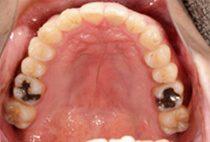

前歯のガタガタを気にして来院されました。人前でお話をするお仕事のため、なるべく目立たない矯正治療をご希望されました。

右側の噛み合わせに違和感を感じており、見た目だけでなく噛み合わせも改善したいと考えています。

歯並びのアーチを全体的に大きくし、部分的に歯の大きさを少しずつ小さくすることで歯を並べるスペースを作りました。インビザラインの透明なアライナーは、治療期間中、周りに気を使うことなく順調に治療が終わりました。

噛み合わせは左右対称的に噛めるようになり、治療前の違和感がなくなりました。